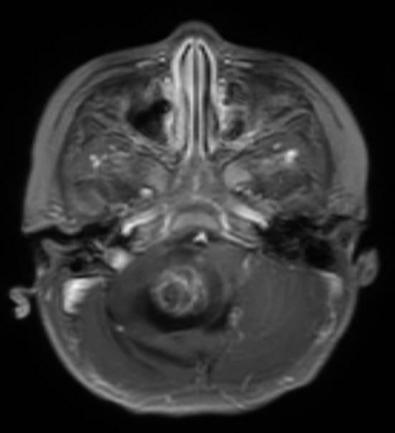

临床资料: 女, 2岁

患者详情: 主诉:行走不稳,饮水呛咳20余天 女童2岁2月,患儿于20天前无明显诱因出现行走不稳,持物不稳,饮水时出现呛咳,进食后呕吐,呕吐物为胃内容物,伴有头疼,无共济失调、视力减退,当地医院查头颅CT及MRI提示颅内占位,建议上级医院就诊。遂就诊于我院查头颅CT提示后颅窝占位并梗阻性脑积水,室旁脑白质水肿,MRI提示后颅窝右侧小脑延髓池及桥小脑脚区不规则囊实性肿瘤,病变与小脑半球及小脑蚓部部分界不清,病变内实性成份内可见弥散受限及增强,向下延伸至枕骨大孔水平以下10mm,脑干及小脑明显受压变形。 自发病以来,患儿精神、体力、食欲食量及睡眠情况无特殊。 既往史、个人史及家族史无特殊。

取材部位: 后颅窝占位

影像学检查:(点击查看大图)